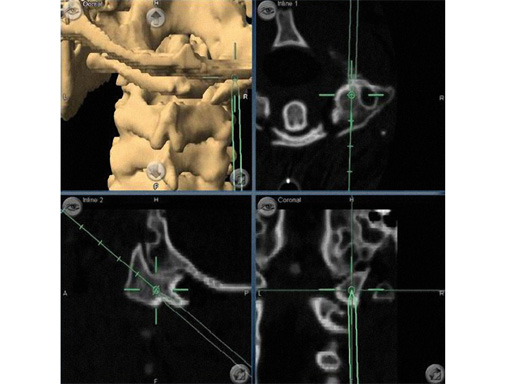

Two recent clinical studies demonstrated improved screw accuracy with isocentric image-intensification-based CT navigation compared to conventional image intensification in > 300 patients undergoing minimally invasive lumbar fusion [9, 10]. Stereotactic navigation is especially useful in patients with more complex anatomy, such as significant spondylolisthesis or degenerative scoliosis. For example, the combination of microsurgery, tubular access approach, CAS and modern instrumentation technology allow decompression and reduction of lumbar spondylolisthesis and stenosis with minimal blood loss and injury to the surrounding musculature (Fig 5). Navigation can also be used to determine the best trajectory for intervertebral cage placement and for transsacral fixation [11]. In the lumbar spine it can be used to determine the length of rods and to align screws during a multilevel fusion so that the percutaneous rod placement is facilitated (Fig 6). Stereotactic navigation has also enabled the minimally invasive resection of odontoid masses via a transnasal route, which is a significant improvement when compared to conventional maximally invasive transoral surgery [12, 13] (Fig 7).

Fig 6ab a Intraoperative screenshot of multilevel lumbar instrumentation. By simulating multiple screws a screw angle and trajectory can be chosen that will facilitate smooth insertion of rods. Distance between screws and rod length can also be determined.

b Postoperative lateral x-ray in same patient. This case combined a lateral translumbar approach for interbody fusion L2L4, a transsacral discectomy, instrumentation, and fusion for L4S1 and percutaneous pedicle screw instrumentation from L2S1 using 3-D-nav.